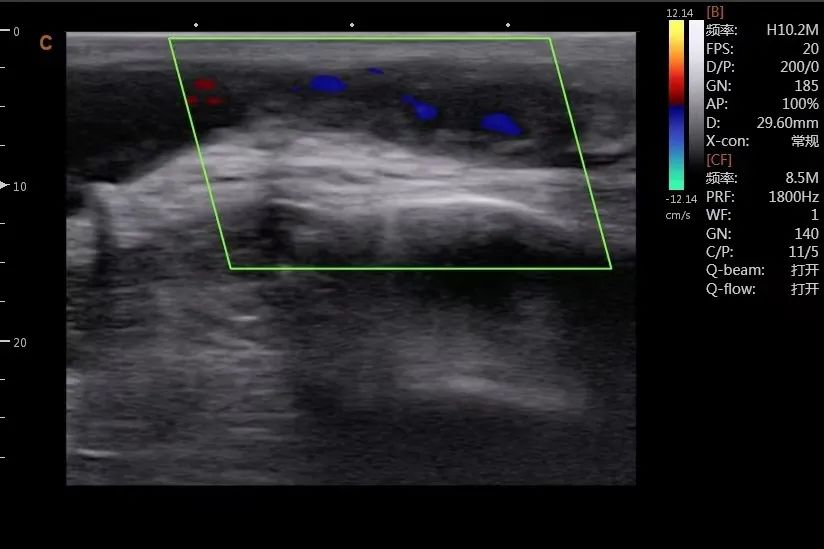

病例1:患者动静脉内瘘流出道静脉狭窄并血栓形成,术前超声探查未见明显血流信号